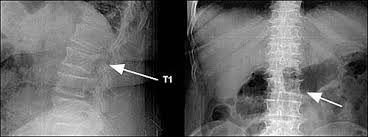

A t12 or l1 compression fracture most commonly happens as a wedge fracture, which occurs when the front part of the vertebra collapses compression fracture treatment options vary depending on the cause.

I have lumber compression fracture and i want to know how much time i need to rest in bed, currently im having totally bedrest even my wife gives me food by her hand only i standup for toilet so im in very depression and also demotiveted please help me someone does it heal by itself? This collapse can also cause pieces of bone to press on. Fluoroscopic view of a kyphoplasty procedure. In these situations, the fractures. Over the weekend i have been experiencing pins and needles in my right hand and arm, a sensation of someone pouring cold water on my left thigh and. At two months from injury, the fracture is probably still not fully stable as compression fractures take about 3 months to heal. Lumbar compression fractures can be a devastating injury, therefore, for 2 reasons. Are there effective ways to treat a compression fracture with physical therapy? The fracture looks like more of a compression fracture than a burst fracture (there is no retropulsion of the l1 body posteriorly). Anteroposterior and lateral radiographs of an l1 osteoporotic wedge compression fracture. Nonsurgical options include activity restrictions, physical therapy, and treating osteoporosis. Burst compression fracture of the l1 vertebral body is associated with a 35% loss of vertebral body height. Vertebral compression fractures (vcfs) occur when the bony block or vertebral body in the spine collapses, which can lead to severe pain, deformity and loss of height.

Spinal Trauma Traumatic Fractures Matthew D Hepler M D

Spinal Trauma Traumatic Fractures Matthew D Hepler M D from southfloridabackspineandscoliosis.com